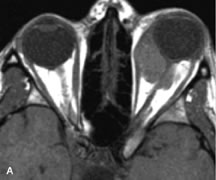

Inflammatory and Lymphoproliferative Lesions

Inflammatory conditions of the orbit, both idiopathic (inflammatory pseudotumor) and those of known causes, have been found to be hypointense to fat and isointense to muscle on Tl-weighted studies and isointense or slightly hyperintense to fat on T2-weighted images (Fig. 21).50,64,69 The more fibrous or sclerosing varieties have less signal intensity on T2-weighted images. Marked enhancement is seen in pseudotumor infiltrates after gadolinium administration.70 The same signal characteristics are demonstrated in patients with Tolosa-Hunt syndrome, with mass lesions seen in the cavernous sinuses and orbital apices.71

Fig. 21. A. T1-weighted MR scan demonstrates diffuse enlargement of both the superior rectus and levator palpebrae superioris muscles (single arrows). The involvement of the tendinous insertions and preseptal soft tissues (open arrows) as well as lack of involvement of other muscles helps differentiate this entity from thyroid-associated orbitopathy. B and C. Postcontrast fat-suppressed T1-weighted MR scans demonstrate extensive enhancement of the involved muscles as well as the preseptal (open arrows) and perinuscular tissues (double arrows).